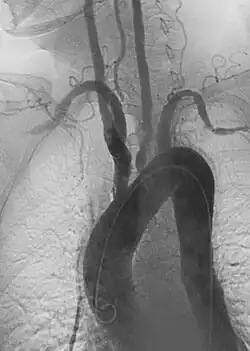

![]() Angiogram ukazujący zapalenie tętnic Takayasu. | |

- angiografia wykazuje zmianę zwężającą naczynie tętnicze